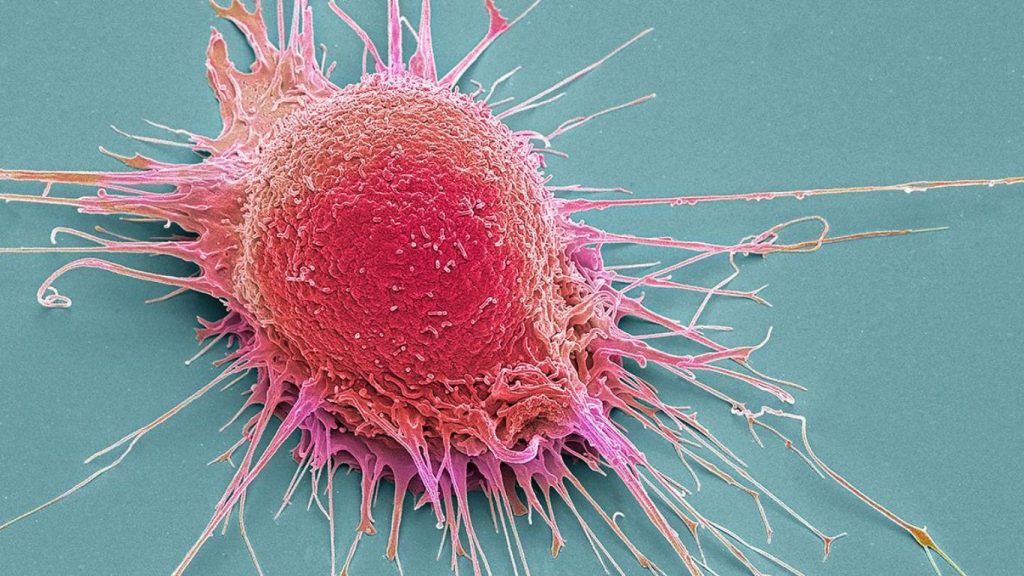

वायु प्रदूषण में मौजूद कैंसरजन तत्व कैंसर के बढ़ने की वजह बनेंगे। खराब एयर क्वालिटी में रहने से कैंसर सेल्स की ग्रोथ में बढ़ोतरी होगी और यह मरीज के लिए गंभीर स्थिति पैदा कर सकती है।